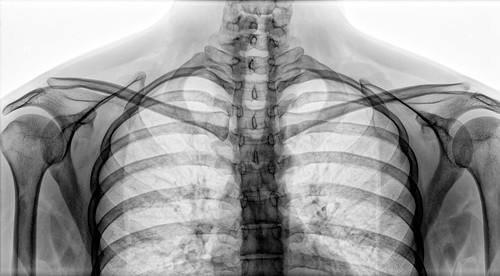

Рентгенография ключиц (со снимком)

Снимок выполняет ряд функций: прямая задняя проекция нужна для диагностики перелома. Цель снимка в прямой передней проекции – это выявление костной структуры ключицы. Снимок в аксиальной проекции нужен для определения направления смещения обломков ключицы.